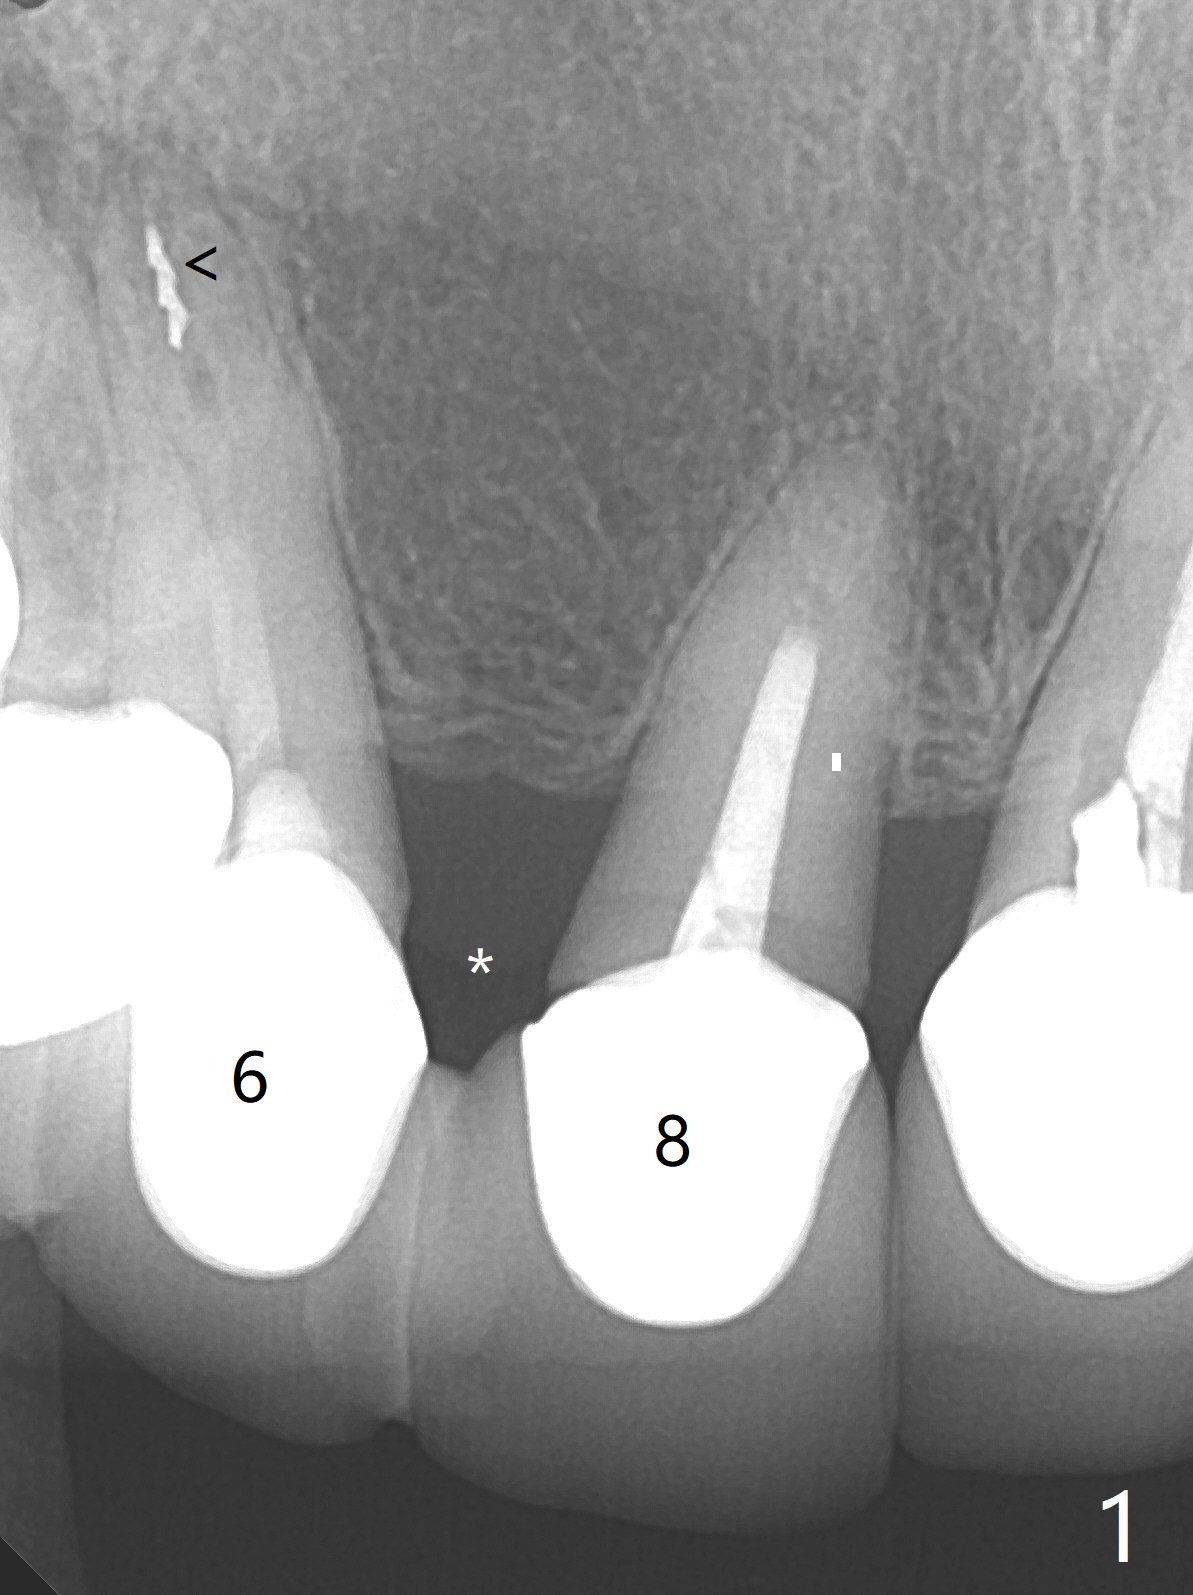

A 67-year-old woman has multiple restoration (difficult for guide preparation). The tooth #6 fractures equigingival with a separated file (Fig.1 <). Because of missing #7, the gingival embrasure between #6 and 8 is large (*). To reduce it, the mesial crest will be trimmed by using 6 mm profile drill after placement of a 3.5x13 mm FC implant (low bone density) and a narrow temporary abutment is going to be used to squeeze the papilla coronally and mesially. In a coronal section, osteotomy will be initiated in the middle of the palatal slope of the socket (Fig.2). A 4 mm x15 degree ~3 mm cuff angled abutment may be used before impression. Take preop photos to show the large gingival embrasure between #6 and 8. The other way to reduce the gingival embrasure is to place an implant mesially. It appears that a 3.5 mm implant is too large for the mesial ridge (Fig.3), while a 2.5 mm one is proper (Fig.4,5).